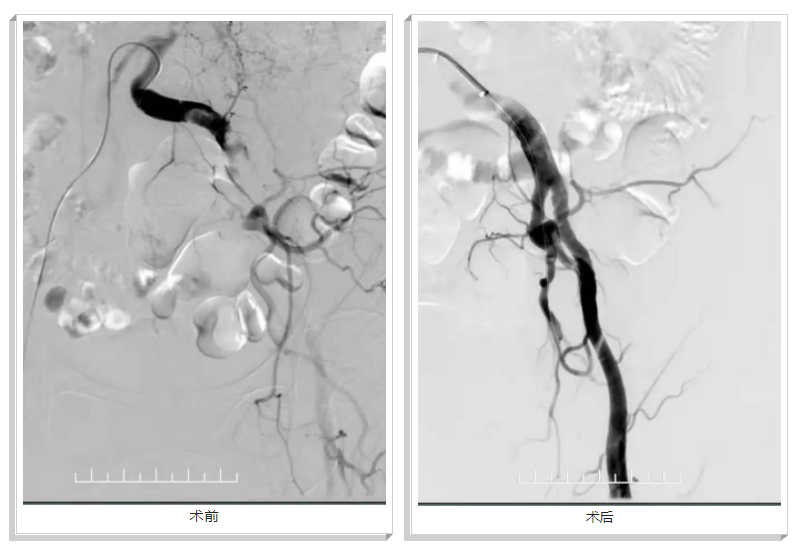

經(jīng)過(guò)完善的術(shù)前準(zhǔn)備,手術(shù)如期而至。術(shù)中造影顯示左下肢動(dòng)脈多處血栓并節(jié)段性閉塞。經(jīng)過(guò)straub機(jī)械血栓切除系統(tǒng)取栓后,成功將左下肢動(dòng)脈血栓取出,術(shù)后血液通暢,左下肢皮溫恢復(fù),膚色轉(zhuǎn)紅潤(rùn),患者及家屬對(duì)術(shù)后效果高度滿(mǎn)意。